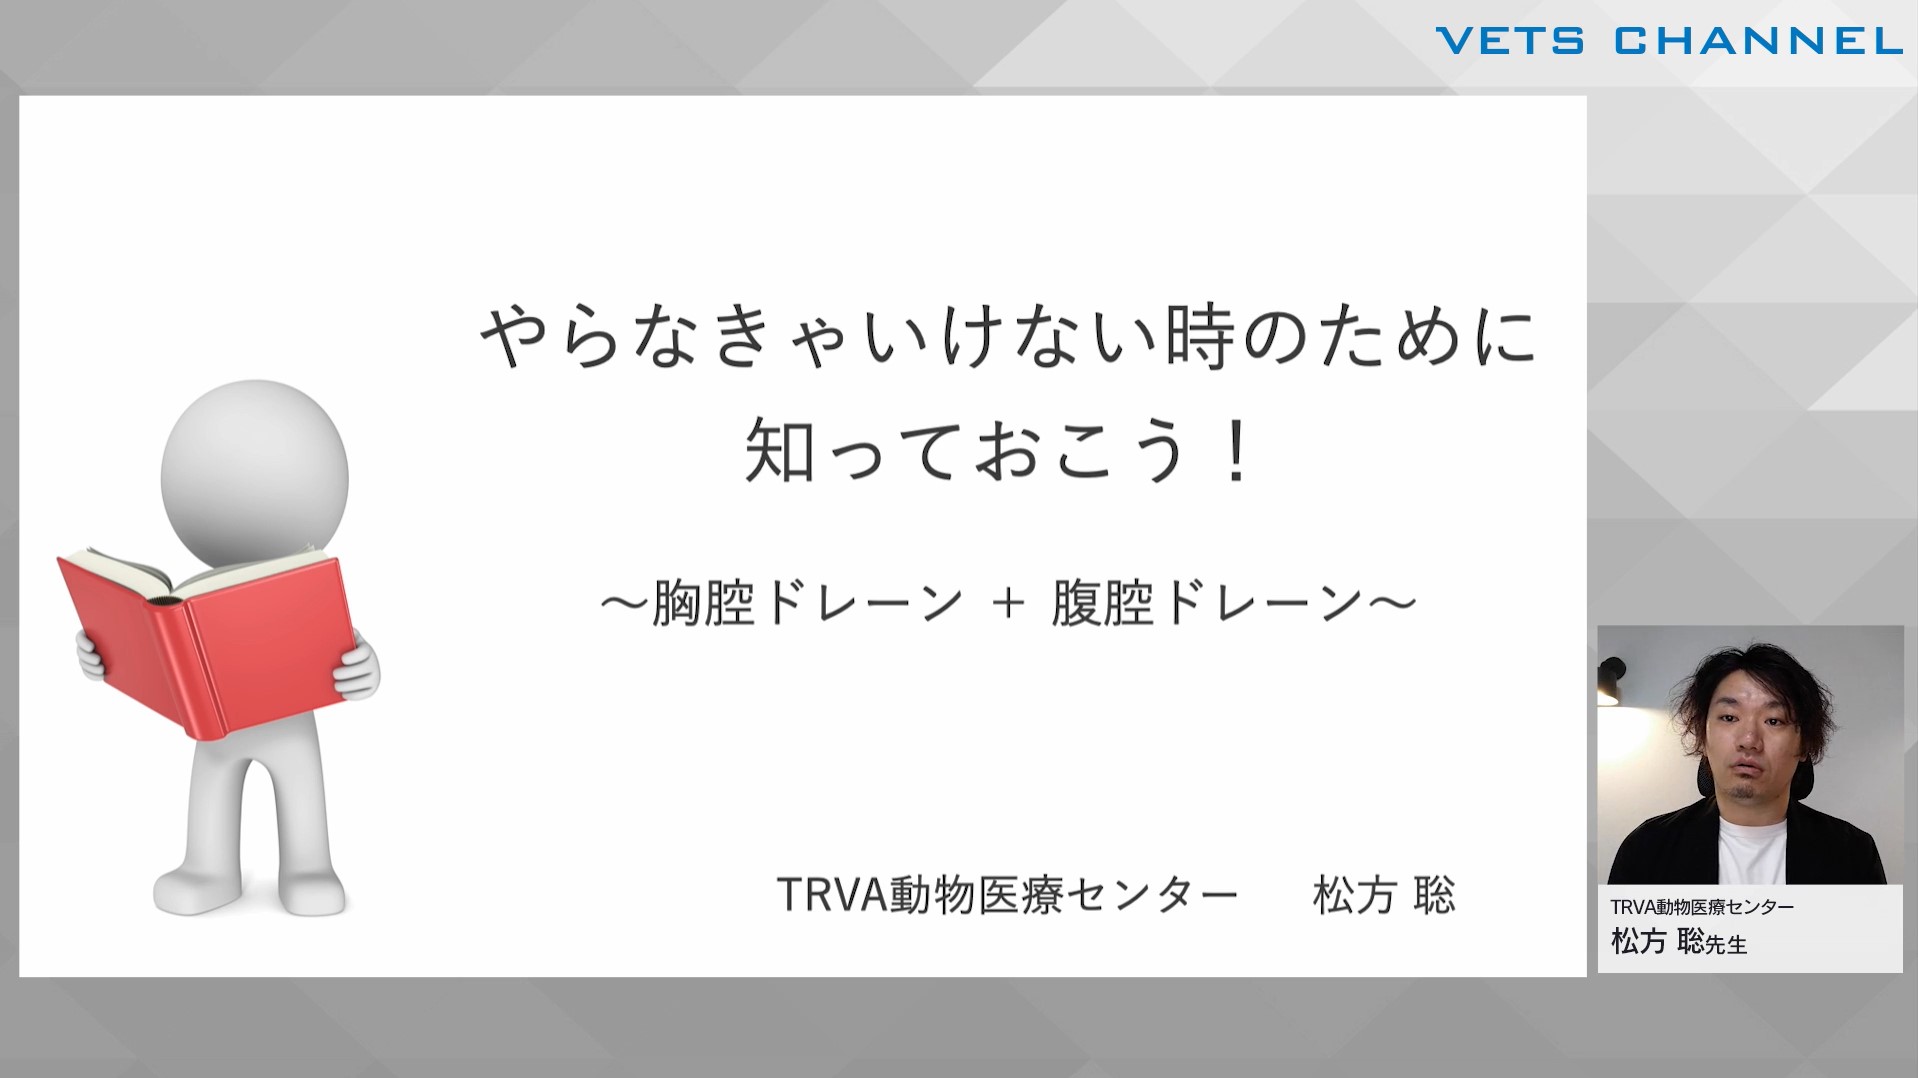

やらなきゃいけない時のために知っておこう! 胸腔ドレーン・腹腔ドレーン

- テクニック

- 軟部外科

- 救急科

- 救急疾患

松方 聡先生(TRVA動物医療センター)

50分

2024/12/27